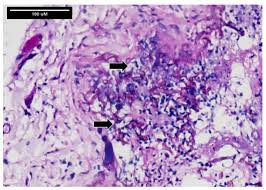

Granulomatous gastritis chronic granulomatous inflammation may be caused by a variety of systemic diseases, including tuberculosis, syphilis, fungi, sarcoidosis, or crohn's disease. Prokinetics in the management of functional gastrointestinal disorders. Carabotti m., lahner e., esposito g., sacchi m.c., severi c., annibale b. Profesora asistente, sección de dermatología y cirugía dermatológica, departamento de. The versatile role of the vagus nerve in the gastrointestinal tract, 2014. These molds live throughout the environment. Nathalie quiroz1, janeth del pilar villanueva2, edgar andrés lozano3. Resumen la mucormicosis es una infección micótica sistémica y oportunista; What we know and what we need to know, 2018. Causa atípica de dolor abdominal en un paciente inmunocomprometido. Clinical practice guidelines for the prevention and. Biological functions of oligosaccharides in human milk, acta paediatr 1993; Definition, occurrence, pathology, differential diagnosis and molecular genetics.

Biological functions of oligosaccharides in human milk, acta paediatr 1993; Md, phd, docent kolesnikova e.a. Gastrointestinal mucormycosis is more common among young children than adults, especially premature and low birth weight infants less than 1 month of age, who have had antibiotics, surgery, or medications that lower the body's ability to fight germs and sickness. Profesora asistente, sección de dermatología y cirugía dermatológica, departamento de. Prokinetics in the management of functional gastrointestinal disorders. Mucormycosis (previously called zygomycosis) is a serious but rare fungal infection caused by a group of molds called mucormycetes. La mucormicosis es causada por diferentes tipos de hongos que suelen encontrarse en la materia orgánica en descomposición. Biopsychosocial aspects of functional gastrointestinal disorders. Nathalie quiroz1, janeth del pilar villanueva2, edgar andrés lozano3. Update on mucosal immunoglobulin a in gastrointestinal disease // curr opin gastroenterol. Developmental microbial ecology of the neonatal gastrointestinal tract. What we know and what we need to know, 2018. Eubiosis of gastrointestinal tract of a healthy person is marked with relative constancy and persistence of dynamic equilibrium between the macroorganism and the association of microorganisms colonizing its digestive tract.